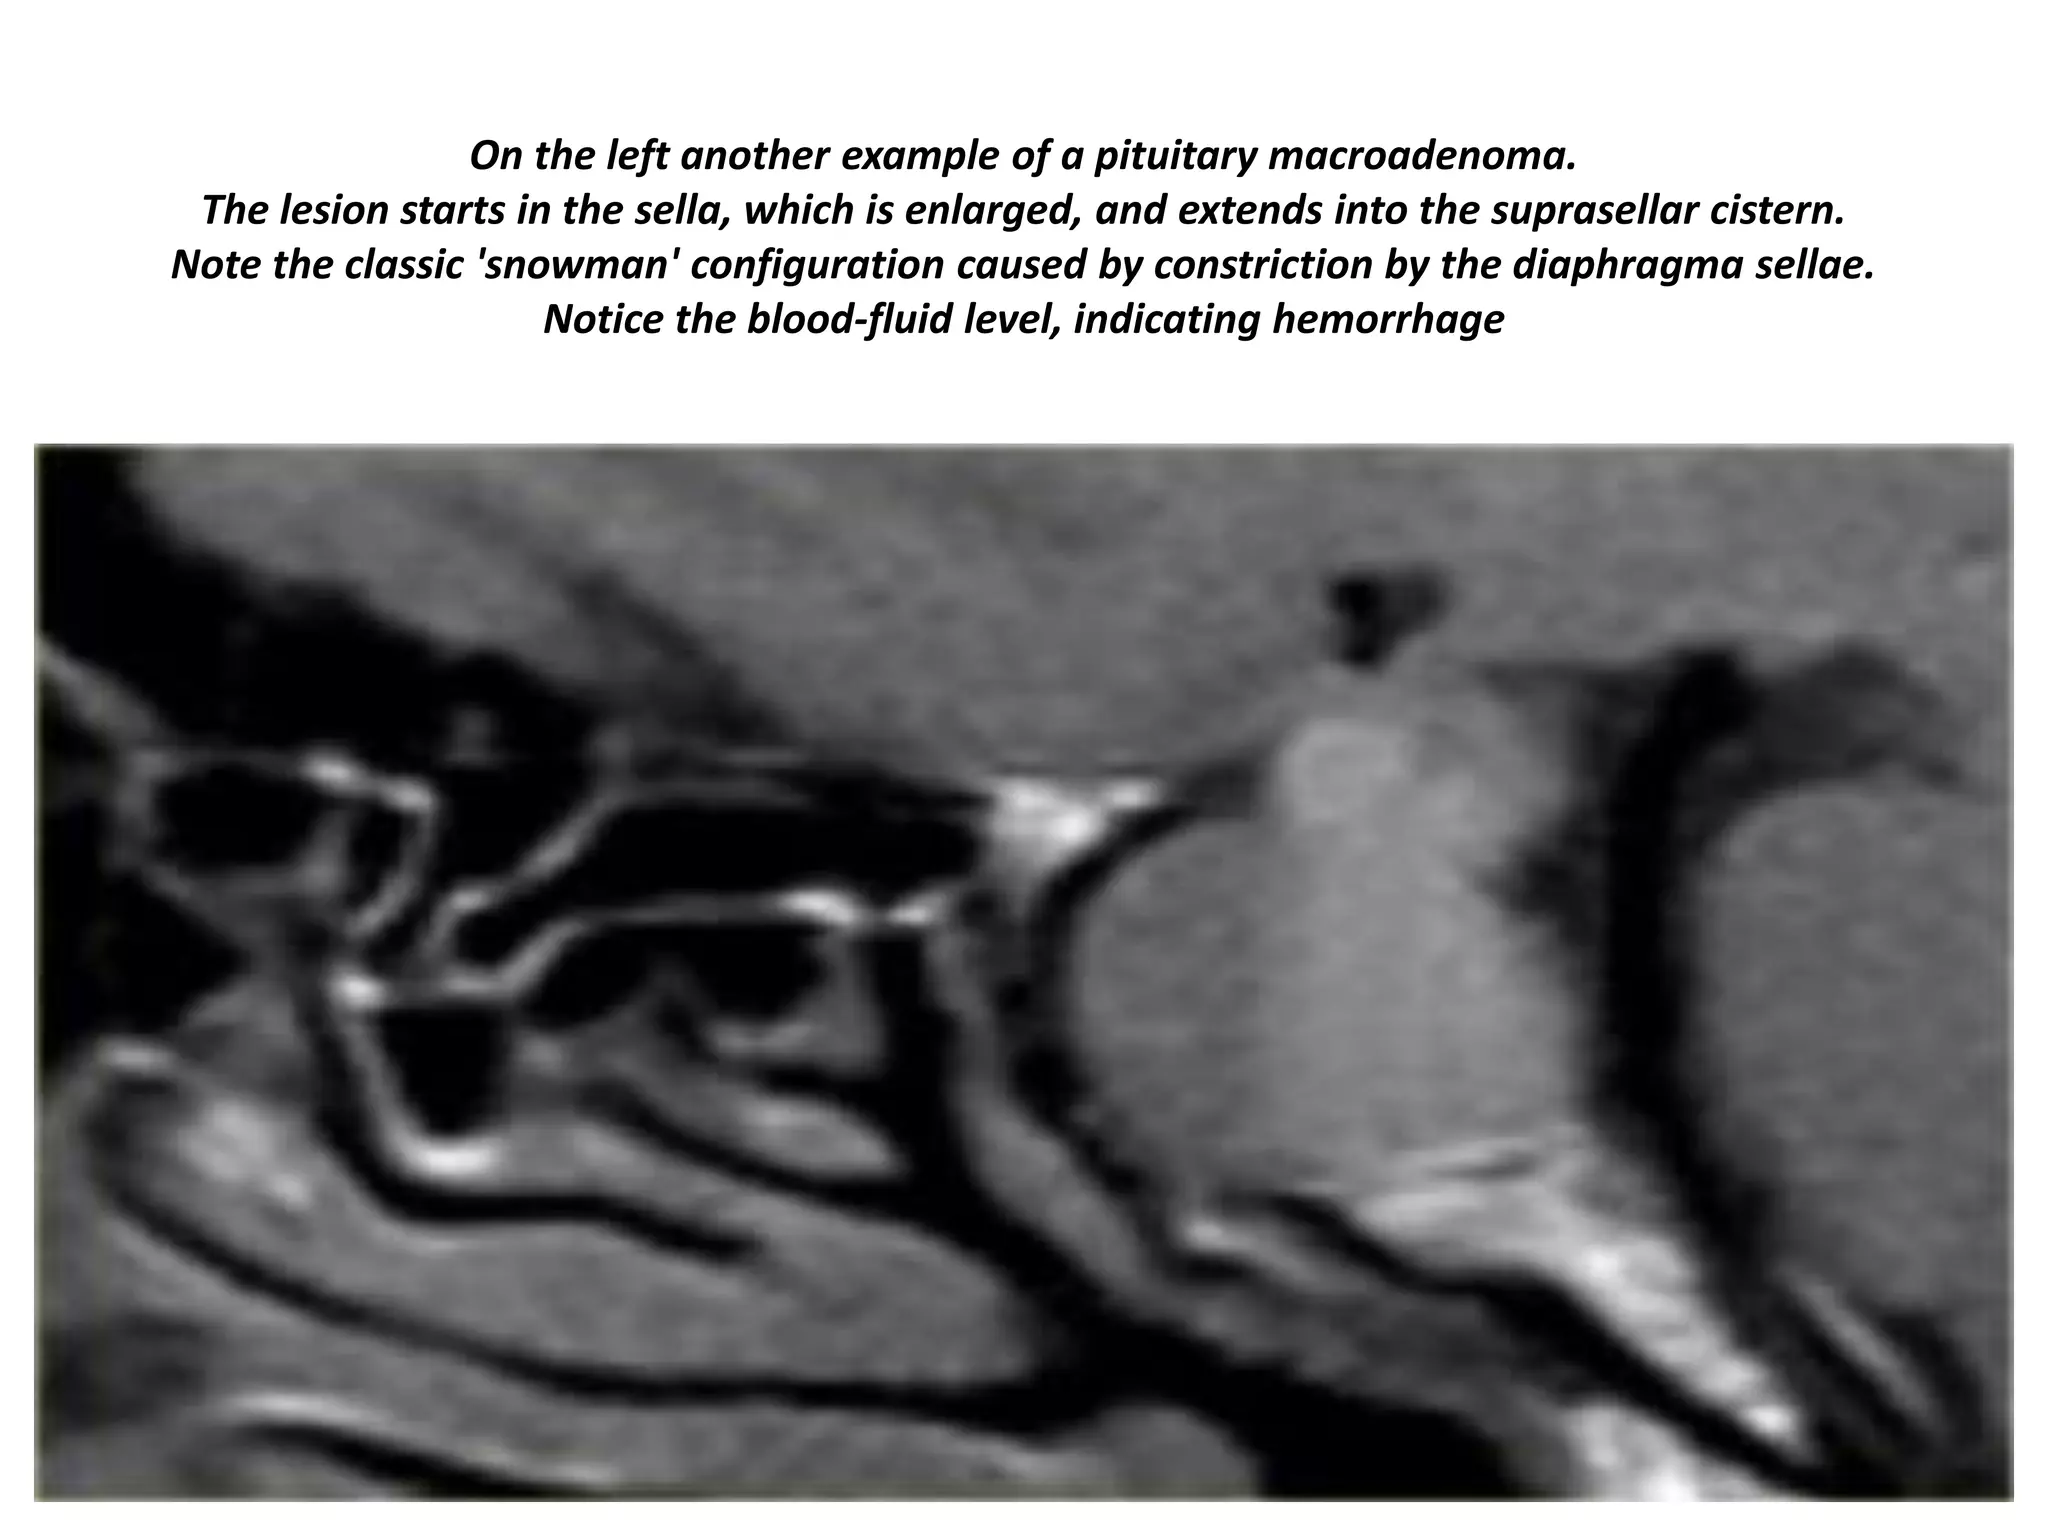

On the left another example of a pituitary macroadenoma.

The lesion starts in the sella, which is enlarged, and extends into the suprasellar cistern.

Note the classic 'snowman' configuration caused by constriction by the diaphragma sellae.

Notice the blood-fluid level, indicating hemorrhage

The usefulness of observing the inclination of the diaphragmatic leaflets was referred to earlier.

On the T2-weighted images on the right you can see that the leaflets are displaced upwards by this

macroadenoma which started in the sella and is growing upwards.

A lesion originating above the sella and growing downwards would push the leaflets in the other

direction (this can be seen with meningiomas for example).